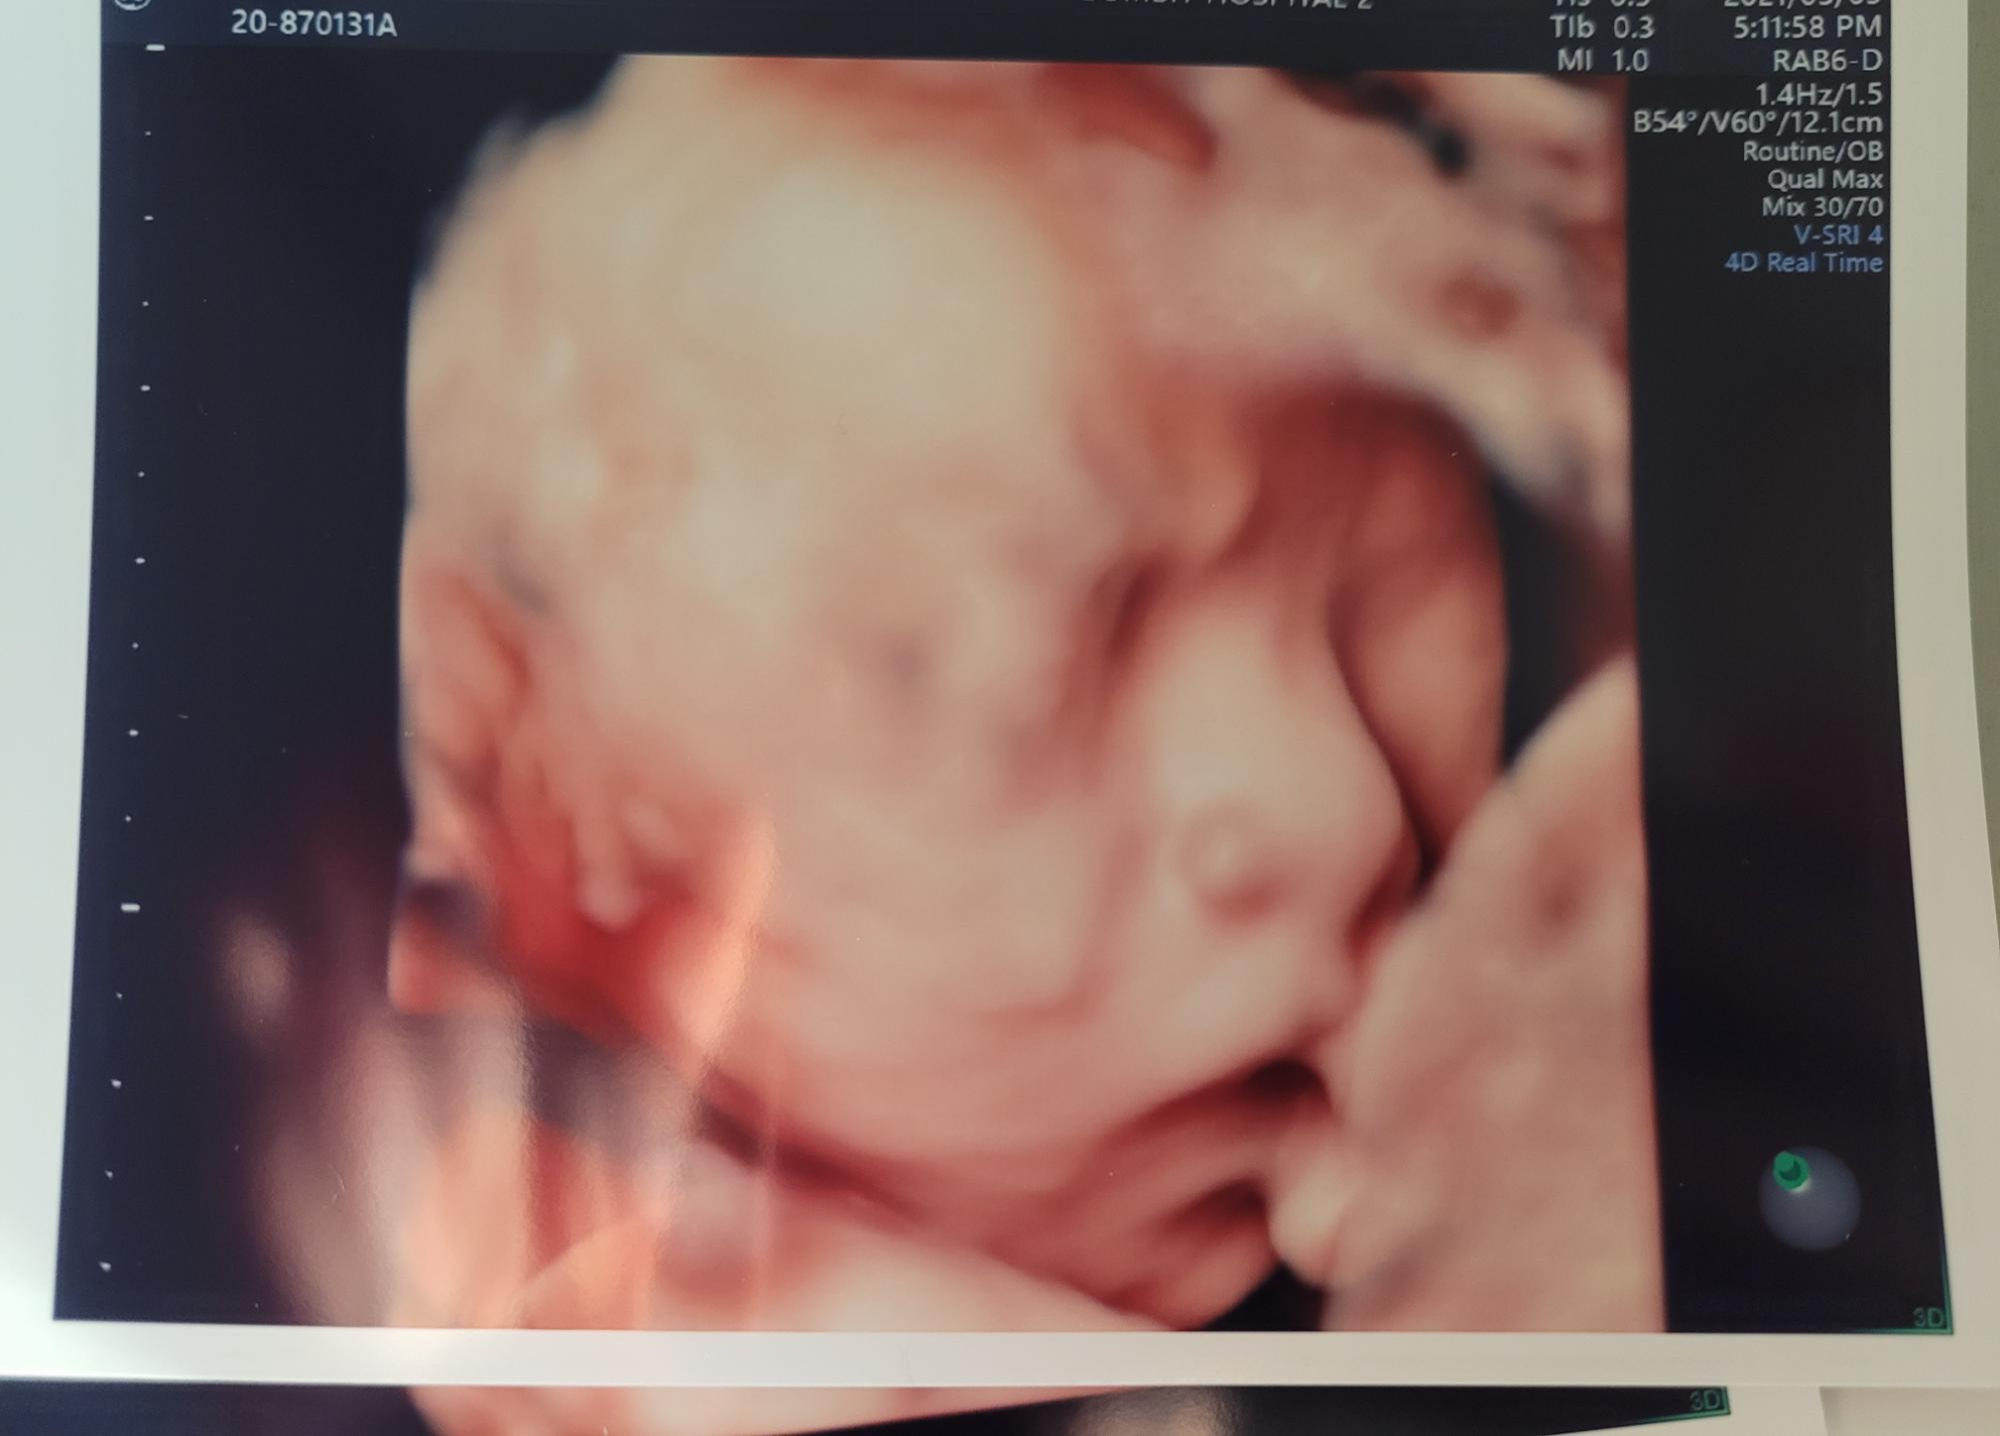

영상으로보면 더 신랑이랑 똑 닮은 우리 행복이^^

컬러 사진으로도 몇장 뽑아주십니다.

막막 또렷하게 정면까지 보여주진않았지만 귀엽더라구요 ㅎㅎ

행복이는 이목구비도 나름 또렷한것같고요^^

누굴닮았나 궁금했는데 딱봐도 남편을 닮았네요ㅎㅎ